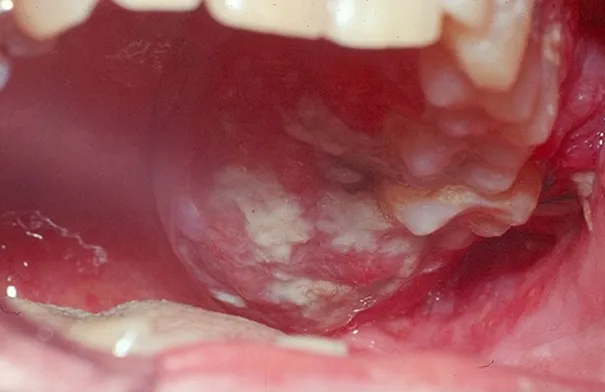

• تحذير طبي: قرحة الفم المستمرة قد تكون علامة على سرطان

• تحذير يخصّ "القرح الفمومية".. أطباء يتحدثون!